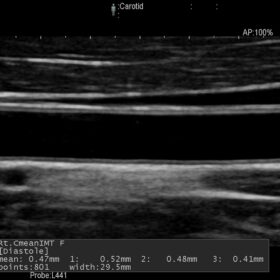

- Blood flow information can be easily acquired. The sharply delineated Doppler waveform is easy to measure.